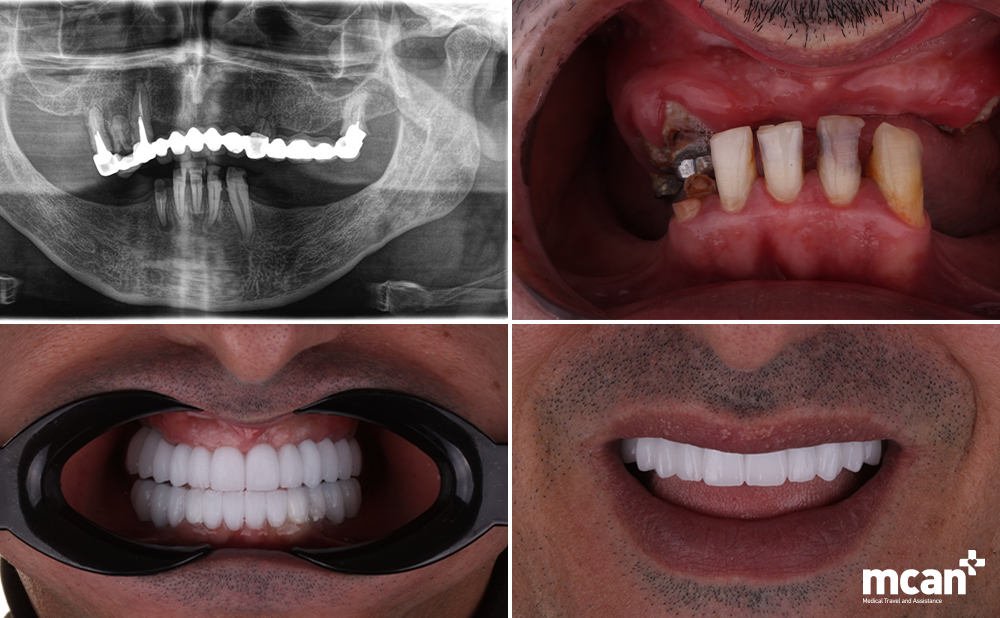

Why Choose MCAN Dental for All-on-4 or All-on-6 Implants in Turkey?

When it comes to full-arch dental implants, precision, expertise, and trust are everything. Whether you’re leaning toward the streamlined All-on-4 approach or the enhanced support of All-on-6, your choice of clinic can determine the success, comfort, and longevity of your new smile.

At MCAN Dental in Istanbul, we specialize in advanced implantology tailored for international patients. Our team of experienced implant dentists uses state-of-the-art diagnostic tools, including CBCT scanning and 3D-guided surgery, to ensure each implant is placed with accuracy and long-term stability in mind.

- Expert Implantologists: Skilled in both All-on-4 and All-on-6 techniques, with thousands of successful cases for patients from around the world.